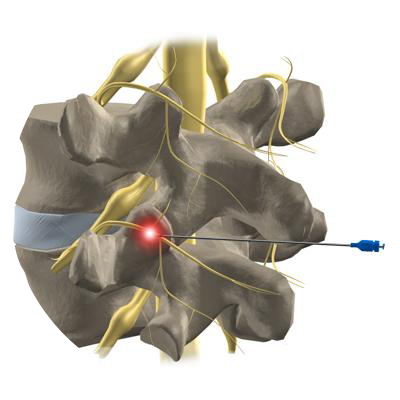

Para lidar com a dor crônica na coluna, é essencial adotar uma abordagem abrangente, que inclua técnicas cirúrgicas avançadas, intervenções minimamente invasivas e uma equipe multidisciplinar dedicada ao manejo da dor. Aliviando a dor crônica na coluna, não apenas melhoramos a função física, mas também elevamos a qualidade de vida dos pacientes.